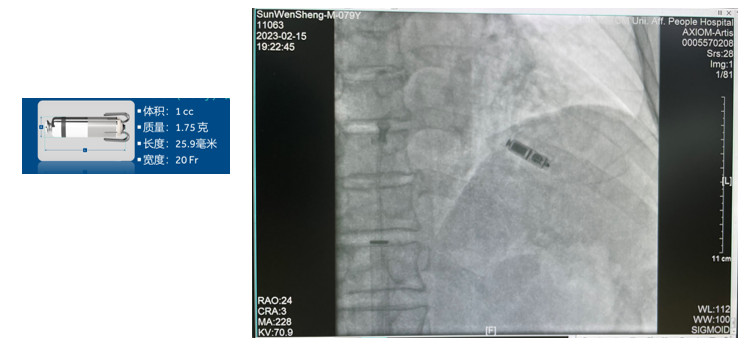

無(wú)導(dǎo)線(xiàn)起搏器植入術(shù)